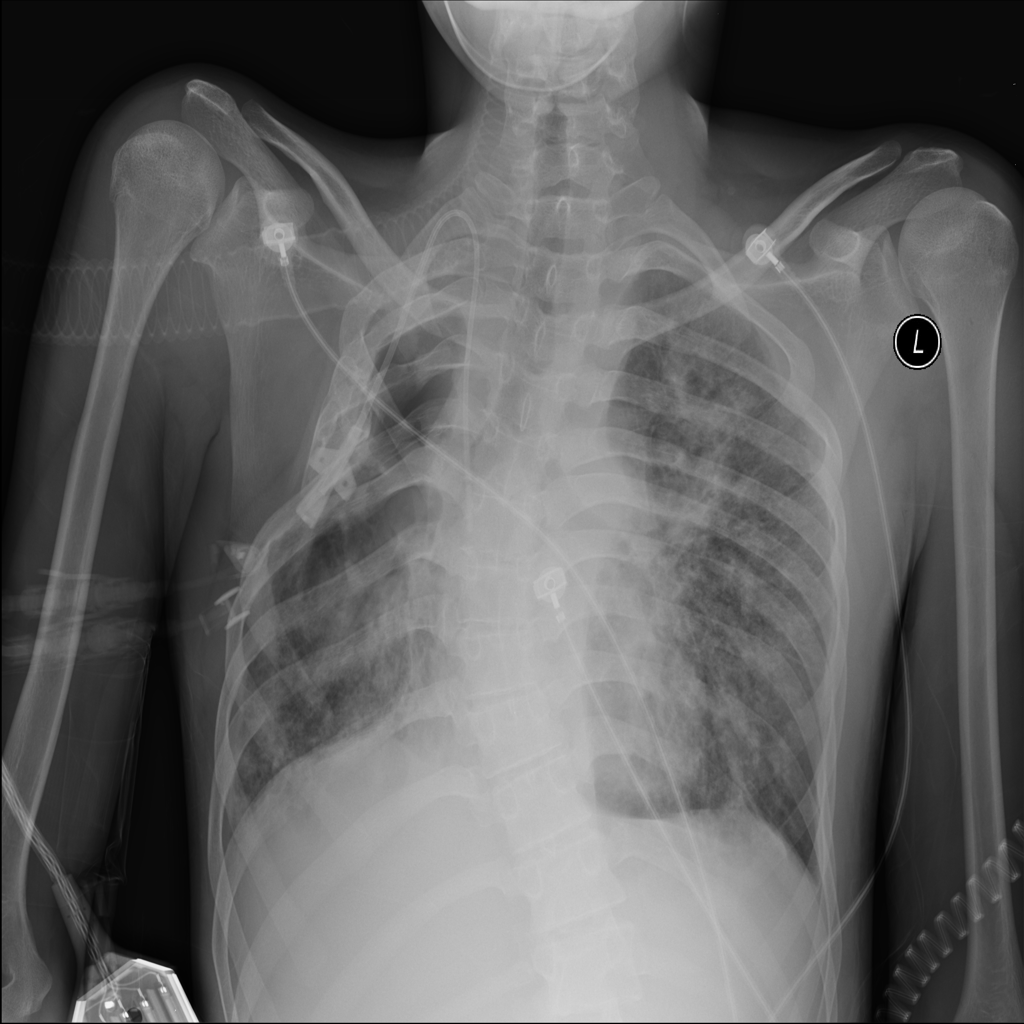

PAT-A380 · IMG-019Pneumonia

PAT-A380 · IMG-019

PA